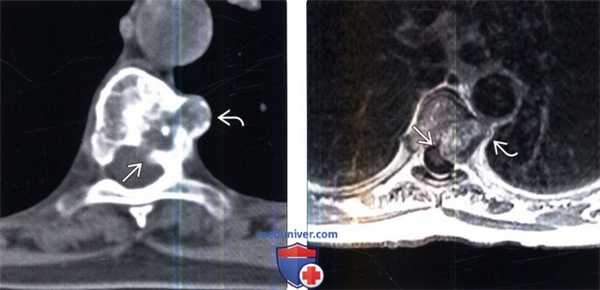

(Слева) Аксиальный КТ-срез: экспансивное литическое объемное образование, содержащее точечные включения кальцинатов. Видны признаки распространения опухоли в эпидуральное пространство и паравертебральные ткани слева от позвонка.

(Справа) Аксиальный срез, Т1-ВИ с КУ: у этого же пациента лучше визуализируется эпидуральный компонент опухоли, оттесняющий дуральный мешок и деформирующий спинной мозг. Видны признаки умеренного гетерогенного контрастного усиления в толще образования. Также отмечается распространение опухоли в паравертебральные ткани слева от позвонка.